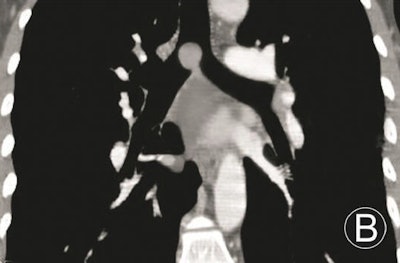

The image data were reconstructed using 1.5-mm sections and 0.5-mm intervals, and postprocessing was performed on a workstation using commercially available software (Advantage Workstation 4.5, GE Healthcare). Axial, coronal, sagittal, and oblique multiplanar reconstruction (MPR) images were acquired section by section, centering on trachea and main bronchus tumors to show the walls, lumina, and adjacent structures, the group wrote.

The results demonstrated that MPR could not only display the locations, morphologies, internal features, and extramural invasions of primary trachea and main bronchus tumors, along with morphologies and extents of luminal stenoses, it could also measure their longitudinal involvement and distances between main bronchus tumors and trachea carinae. However, due to the 2D images, MPR could not provide a 3D effect, according to the researchers.

Volume-rendered images can handily demonstrate locations, morphologies of primary trachea and main bronchus tumors, and morphologies and extents of luminal stenoses, and it can measure the longitudinal involvements and distances between main bronchus tumors and trachea carinae. However, volume rendering can't display the internal features of tumors and extramural invasions, they noted.